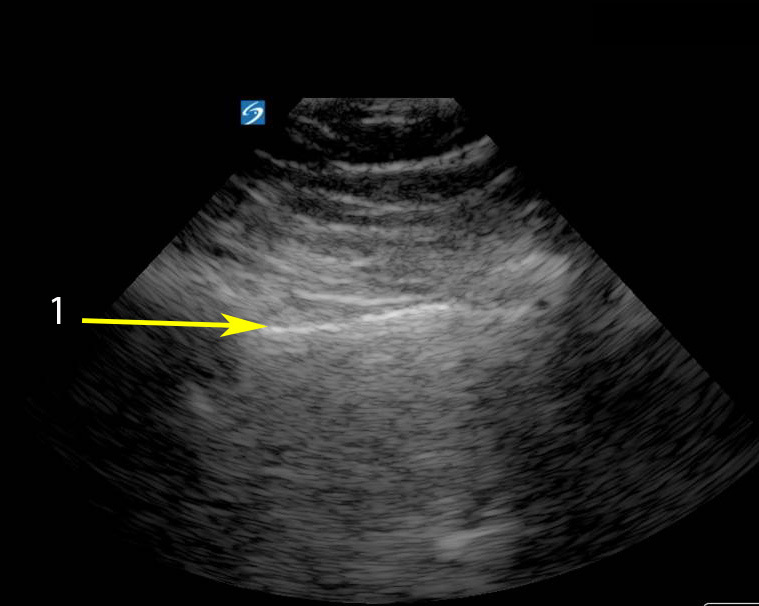

ラングスライディングの段階的番号付き画像

胸膜ライン